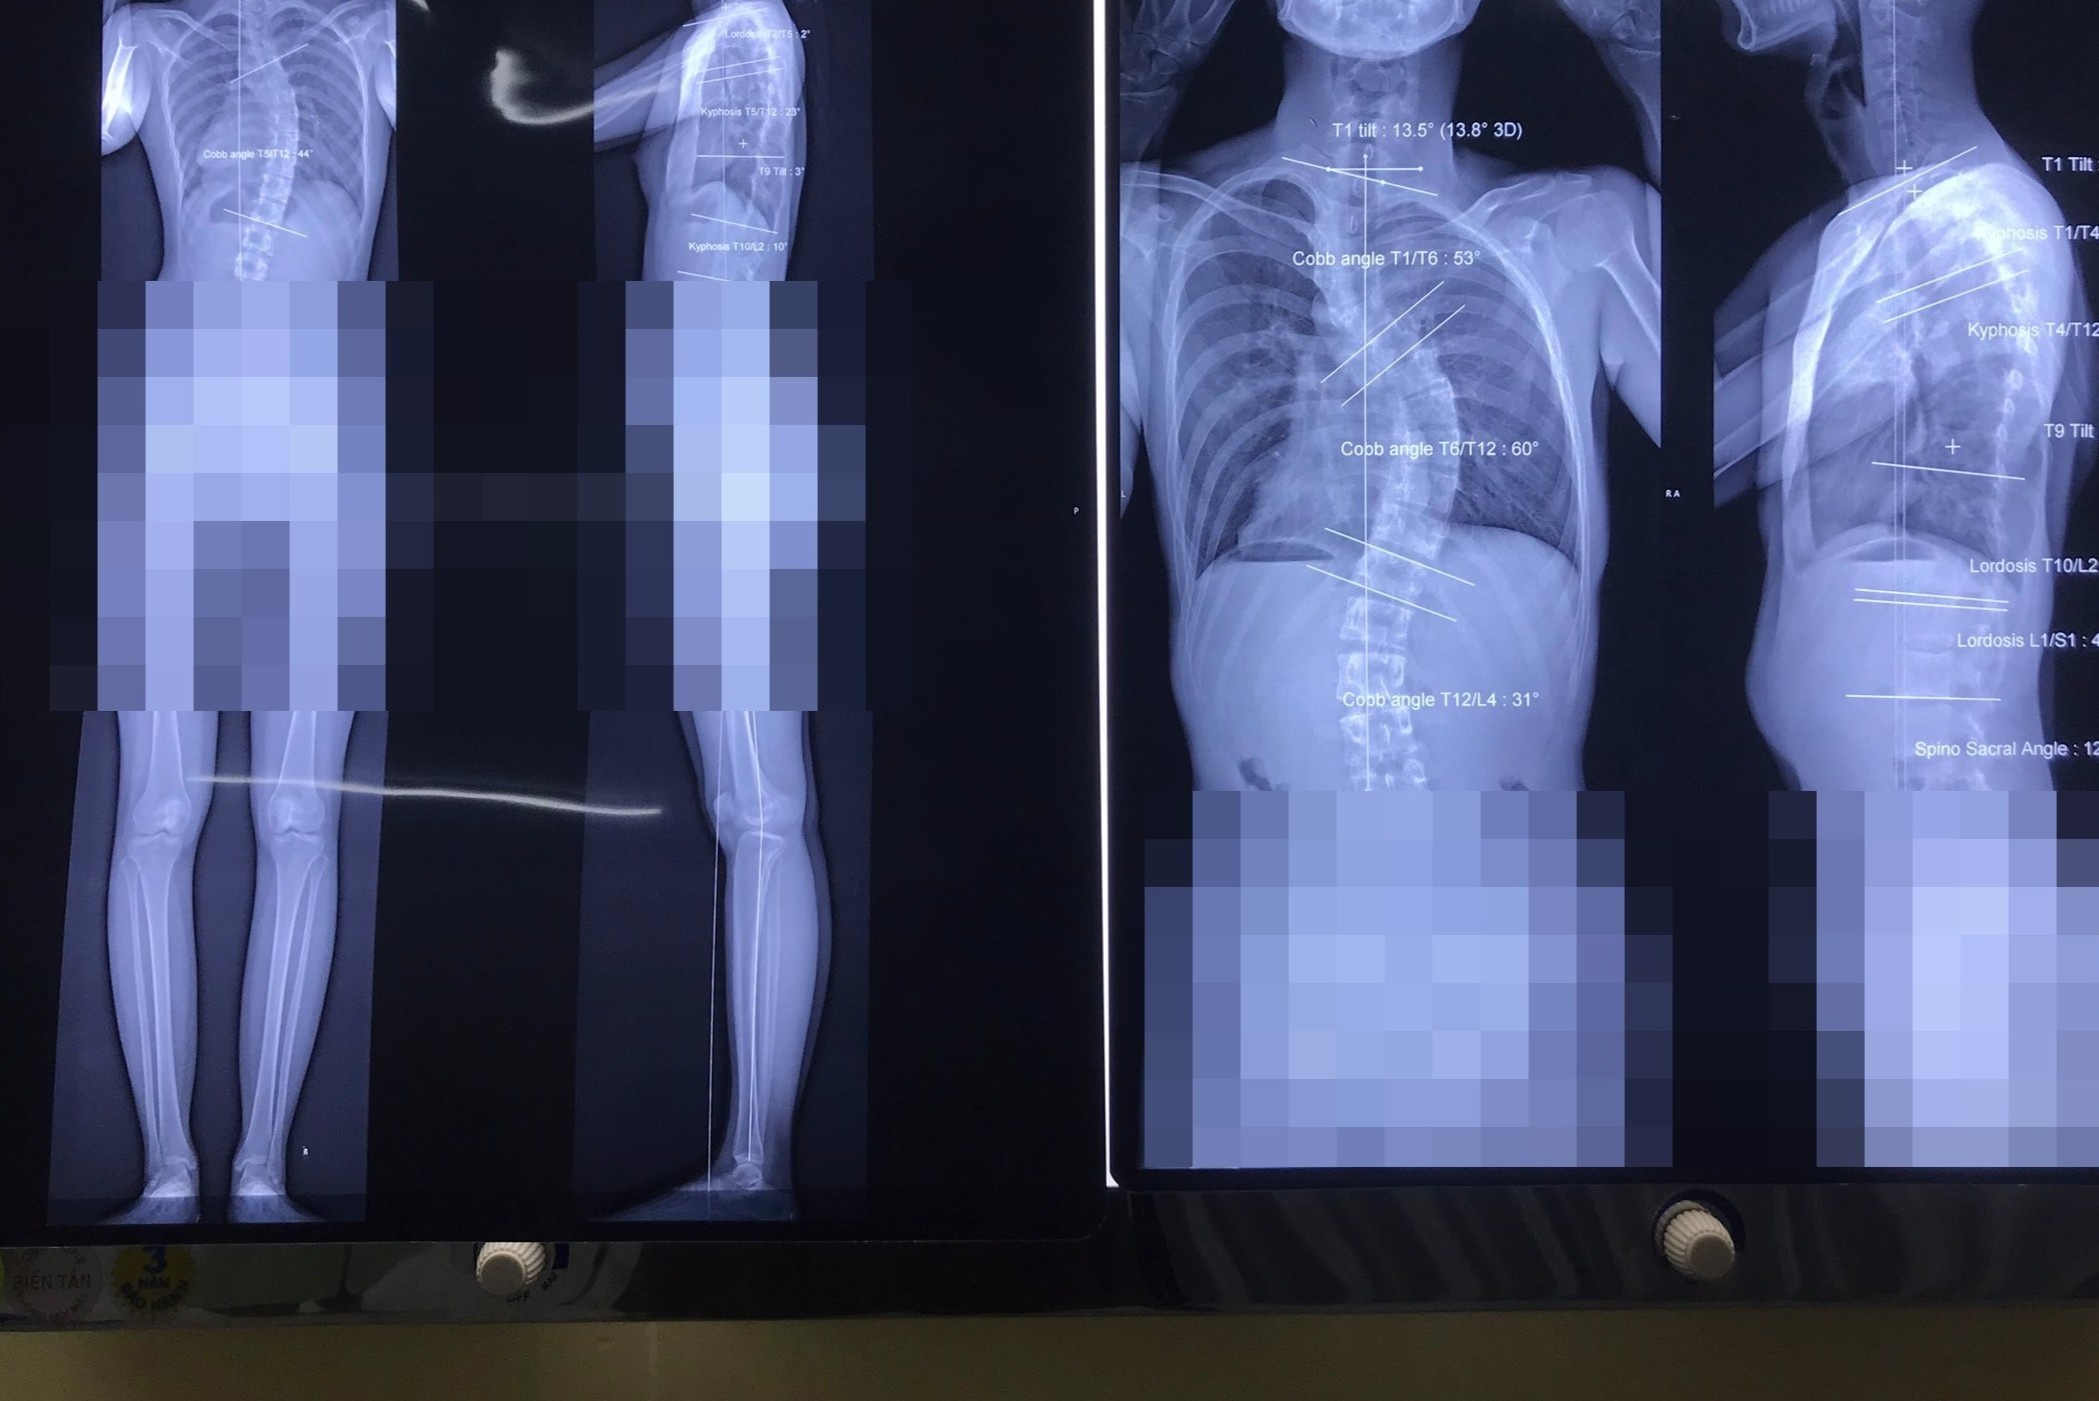

Hình ảnh cột sống biến dạng của một bệnh nhân bị gù vẹo cột sống. Ảnh: Huy Hoàng.

"Do để lâu ngày, căn bệnh này đã biến chứng biến dạng lồng ngực, cột sống bị cong chữ S, chức năng hô hấp cũng thay đổi", bác sĩ Quang Anh cho hay.

Theo bác sĩ Quang Anh, vẹo cột sống là biến dạng của cột sống, trong đó, chúng bị cong lệch sang một bên theo hình chữ C trên mặt phẳng trán. Người bệnh có thể bị cong 2 vị trí trở lên theo hình chữ S.

Một số trường hợp các đốt sống xoay theo mặt phẳng ngang, tùy vị trí cao thấp gây biến dạng hình thể thân trên và lồng ngực hoặc xoay khung chậu thay đổi dáng đi. Các trường hợp phức tạp bao gồm đủ cả gù, vẹo và xoay cột sống.